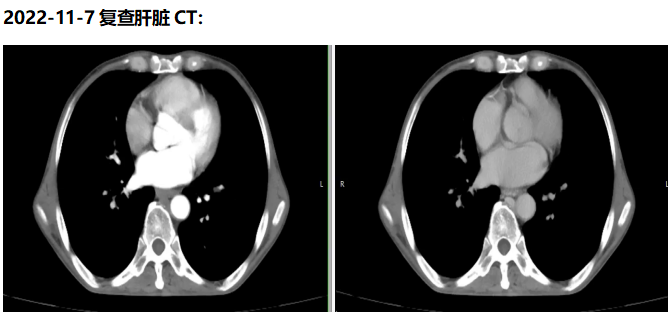

相较其他联合治疗药物,阿帕替尼联合卡瑞利珠单克隆抗体的“双艾”组合,是目前晚期肝癌一线治疗中最长中位总生存期(OS)获益方案,已被证实具有良好的安全性和耐受性,且作为民族原研药物,其可及性更高,患者用药的依从性更好。经MDT讨论,医生最终选用“双艾”组合作为本例患者的一线治疗方法。用药后发现,患者的病灶明显缩小,已达手术可切除标准,建议停药2-4周后行手术治疗。但家属拒绝手术,要求继续靶免治疗。经综合评估,予以患者TACE术局部治疗后继续维持“双艾”方案,术后复查肝脏CT未见疾病进展,未发生严重不良事件,“双艾”方案一直用药至今。这一病例的成功转化充分体现了“双艾”组合具有切实疗效与良好的安全性。近期,“双艾”方案一线治疗晚期肝癌的全球III期随机对照临床研究CARES-310研究也已重磅问世并荣登《柳叶刀》正刊,进一步巩固了“双艾”方案一线治疗晚期肝癌患者的坚实地位。